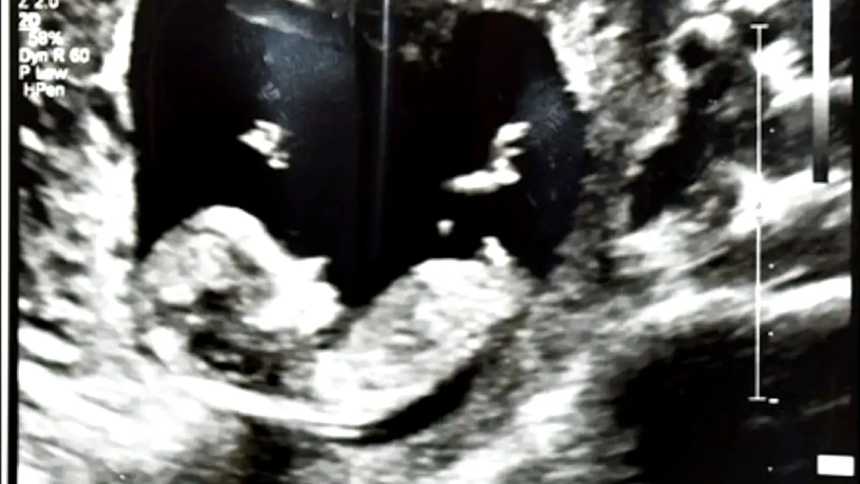

Un hombre llamado Donovan Faison, de 23 años, fue declarado culpable del asesinato de su novia Kaylin Fiengo, de 18 años, quien estaba embarazada al momento de su muerte.